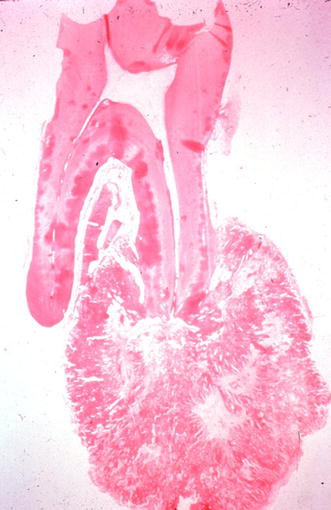

Histologic examination revealed sheets and masses of paucicellular cementum attached to the root of the tooth (Fig. 2). The cementum displayed prominent basophilic reversal lines and cementoblastic rimming (Figs. 3 and 4). The cementoblasts were plump with moderate amounts of cytoplasm, hyperchromatic nuclei, and conspicuous nucleoli. The intervening stroma consisted of loose fibrovascular tissue with scattered multinucleated osteoclast-type giant cells. At the periphery of the lesion, radiating columns of unmineralized tissue were oriented perpendicular to the surface of the lesion.

Fig. 2

Calcified mass fused to the root of a molar tooth